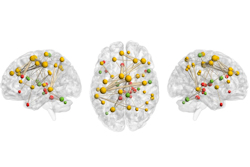

Certain advanced MRI metrics are more useful than others for assessing white matter alterations that could be linked to long-COVID brain fog, according to research results presented May 6 at the International Society for Magnetic Resonance in Medicine (ISMRM) meeting.

A team led by Nicolò Rolandi, PhD, of University College London in the U.K. explored voxel-wise analysis of core white-matter voxels using advanced MRI metrics and neuropsychological scores.

The study dataset included 25 healthy control participants and 47 with long COVID who were scanned and clinically assessed between June 2020 and August 2023. MRI data were acquired using a Philips Ingenia CX 3T scanner with the product 32-channel head coil, the group noted.

The investigators used quantitative magnetization transfer, inversion recovery, and diffusion-weighted imaging to calculate advanced MRI metrics. They assessed changes of bound pool fraction (BPF), spin-spin relaxation time of the bound pool (T2B), longitudinal relaxation time (T1), fractional anisotropy (FA), mean diffusivity (MD), orientation dispersion index (ODI), and neurite density index (NDI).

Each showed regional microstructural alterations at a voxel-wise level. The team noted that voxel-wise analysis of the core skeleton of white matter used 5,000 permutations and corrected for multiple comparisons using threshold-free cluster enhancement (TFCE).

The insights generated could add to the medical community's understanding of the involvement of white matter alterations as either a risk factor or consequence of long COVID. For ISMRM, the team noted four interesting findings:

- T2B widespread alterations were observed in the frontal lobe, diencephalon, and left occipital lobe, with increased T2B values being observed in long COVID compared with healthy controls.

- Widespread alterations of BPF were found in the frontal lobe and more localized to the left temporal and occipital lobes, with reduced BPF being observed in long COVID.

- No alterations were found using FA, MD, ODI, and NDI.

- No correlation was found between SDMT and MRI metrics.

This research adds to previous studies that have shown brain structural alterations following COVID-19. It is important because it highlights possible mechanisms associated with brain fog in people experiencing long COVID.

Approximately 30% of people who develop COVID after contracting SARS-CoV-2 experience a variety of symptoms that after 12 weeks, are defined as long COVID or post-COVID-19 syndrome, the authors noted. Lingering issues may include neurological symptoms, such as trouble thinking and concentrating, that are a type of brain fog.

Using MRI would enable a more thorough exploration of the diverse cognitive dimensions affected in people experiencing brain fog and perhaps a better understanding of how white matter alterations are involved, Rolandi and colleagues concluded.